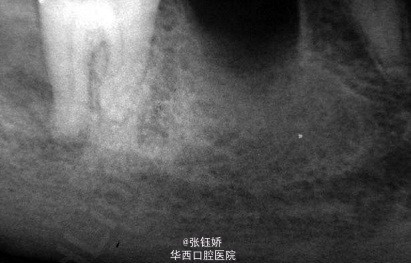

女,56岁,自觉左下磨牙区敏感不适,X线片示36牙已根充,远中根管超填,近中根管欠填,根管预备显示近中根管下段钙化,根尖周见较大暗影。考虑到患者牙合间距离很小不符合根尖手术适应症,故拟行意向性牙再植术。